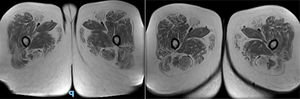

Presentación del casoPaciente de 36 años que consulta por presentar debilidad progresiva en ambos miembros inferiores de inicio distal y progresión proximal, asociada a episodios de rabdomiólisis que se desencadenan ante síndrome febril. Al examen clínico se demuestra la presencia de anquilosis quirúrgica de la articulación del tobillo, debilidad a la flexión del muslo sobre la pelvis 4/5 y de la flexión de la pierna sobre el muslo 4/5, hipotonía muscular y atrofia muscular del compartimento posterior de la pierna y arreflexia de miembros inferiores con reflejos conservados en los miembros superiores (fig. 1). Como antecedentes familiares el paciente refiere haber nacido de parto vaginal, sin antecedentes de hipoglucemia perinatales y con una marcha independiente que se consolida a los 18 meses de edad. Refiere a los 4 años de edad episodios de dolor muscular en los miembros inferiores, con claudicación de la marcha y niveles de CPK 6000, que se desencadenan ante infecciones intercurrentes, y ya a los 7 años de edad la debilidad muscular era fija, con exacerbaciones ante factores gatillantes, dificultando la marcha, por lo que le realizaron una electromiografía digital de los 4 miembros con velocidad de conducción, informándose de polineuropatía axonal, por lo que se le practicó una biopsia de músculo y nervio, donde se objetivaron cambios miopáticos (contornos poligonales, fibras anguladas atróficas estereasa positivo, atrofia neurógena con extenso agrupamiento histoquímico y fibras necróticas y en regeneración) y biopsia del nervio periférico, donde se visualizó una disminución mayor del 35% de fibras mielínicas y onion bulbs (remielinización). Por los hallazgos en la biopsia de músculo se descarta atrofia muscular espinal mediante estudio genético. A los 20 años de edad le realizan la anquilosis bilateral de la articulación del tobillo por estepaje bilateral.

Se solicita RMI de músculos de ambos muslos, donde se visualiza en secuencia T1 la infiltración grasa de músculo sartorio, recto interno, semitendinoso y glúteo mayor bilateral (fig. 2). El estudio de laboratorio reveló una CPK de 141. La espirometría computarizada resultó con insuficiencia restrictiva de grado moderado (CVF65%3,6l y FEV169%3,62l) y la evaluación cardiológica por electrocardiograma y ecocardiograma Doppler transtorácico obtuvo resultados normales (fig. 3). La evaluación oftalmológica fue normal. Ante la sospecha de una posible miopatía metabólica se solicitó dosaje de acilcarnitinas, donde se observó un incremento de C16OH, C18OH, C18:20H y C18:10H, y ante estos resultados se procedió a la evaluación del gen HADHA que codifica la proteína trifuncional (TFP), que tiene 3 subunidades, 3-hidroxiacil-CoA deshidrogenasa de cadena larga (LCHAD), enoil-CoA hidratasa de cadena larga y tiolasa de cadena larga, que actúan en la metabolización de los ácidos grasos de cadena larga, demostrándose la presencia de la variante c.2231delT, la cual promueve un cambio de la matriz de lectura a partir de este punto, con la consecuente creación de un codón de parada prematuro de la traducción proteica (p.Phe744Serfs*7). Esta variante se demuestra en heterocigosis simple (una copia) y es descripta en la base de datos como probablemente patogénica. Según las pautas de interpretación de variantes del Colegio Americano de Genética Medica y Genómica (ACMG/AMP), los términos «variantes patógenas» y «probable variantes patógenas» son sinónimos en un entorno clínico compatible, por lo que ante la presencia de un perfil de acilcarnitina anormal, a pesar de identificarse solo una variante patogénica, se realiza el diagnóstico de deficiencia de LCHAD/TFP al no contar con la posible identificación de la enzima 3-hidroxiacilCoA deshidrogenasa de forma aislada3.

La resonancia magnética muscular muestra patrones de cambios prominentes en STIR que reflejan rabdomiólisis y aumento de la intensidad de la señal en T1 que refleja la infiltración grasa del tejido muscular3.